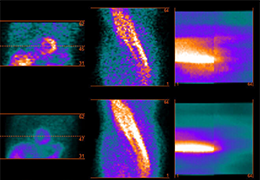

ANYTHINK 经导管主动脉瓣膜置换术分析系统